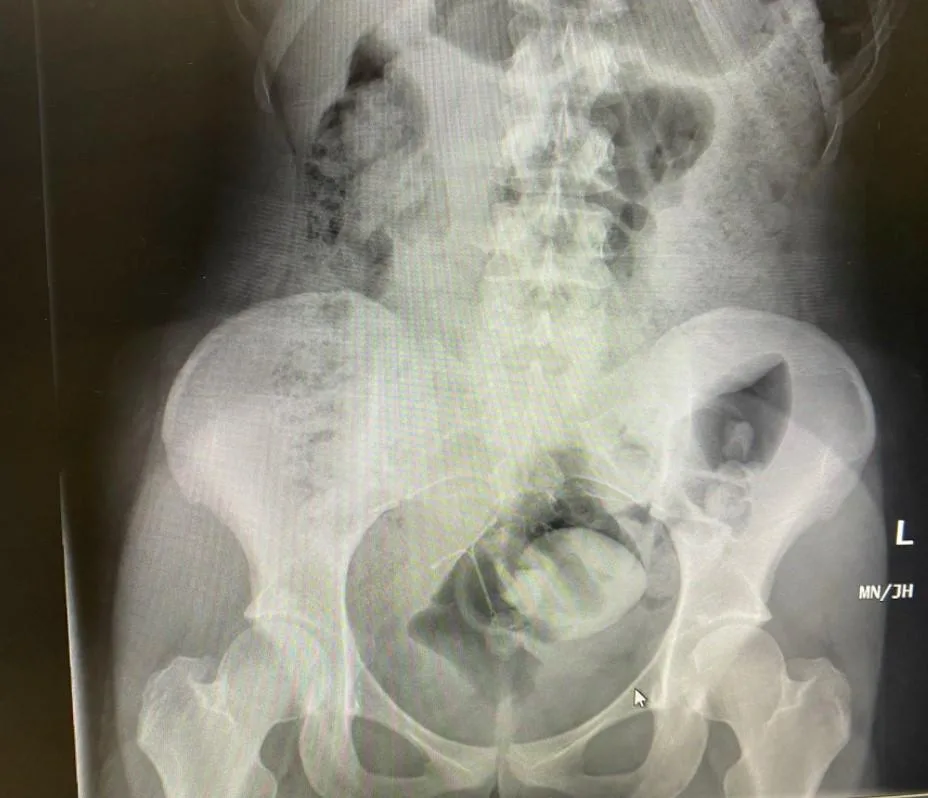

当时她多次尝试把玩具取出,但是努力了一个小时都没有成功,最后只能硬着头皮,到医院急诊室找医生求助。医生替她照了X光,果然发现葫芦状的情趣玩具卡在萝希的直肠里。

情趣玩具卡在萝希的直肠里(图片来源:rosieesunshine社交媒体账号)